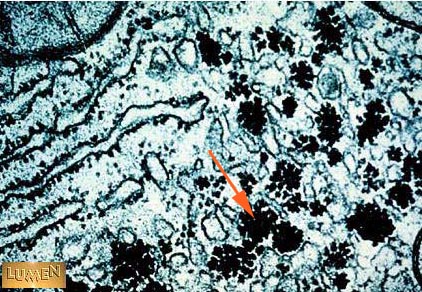

What are the clumps of dark material indicated by the arrow?

Glycogen